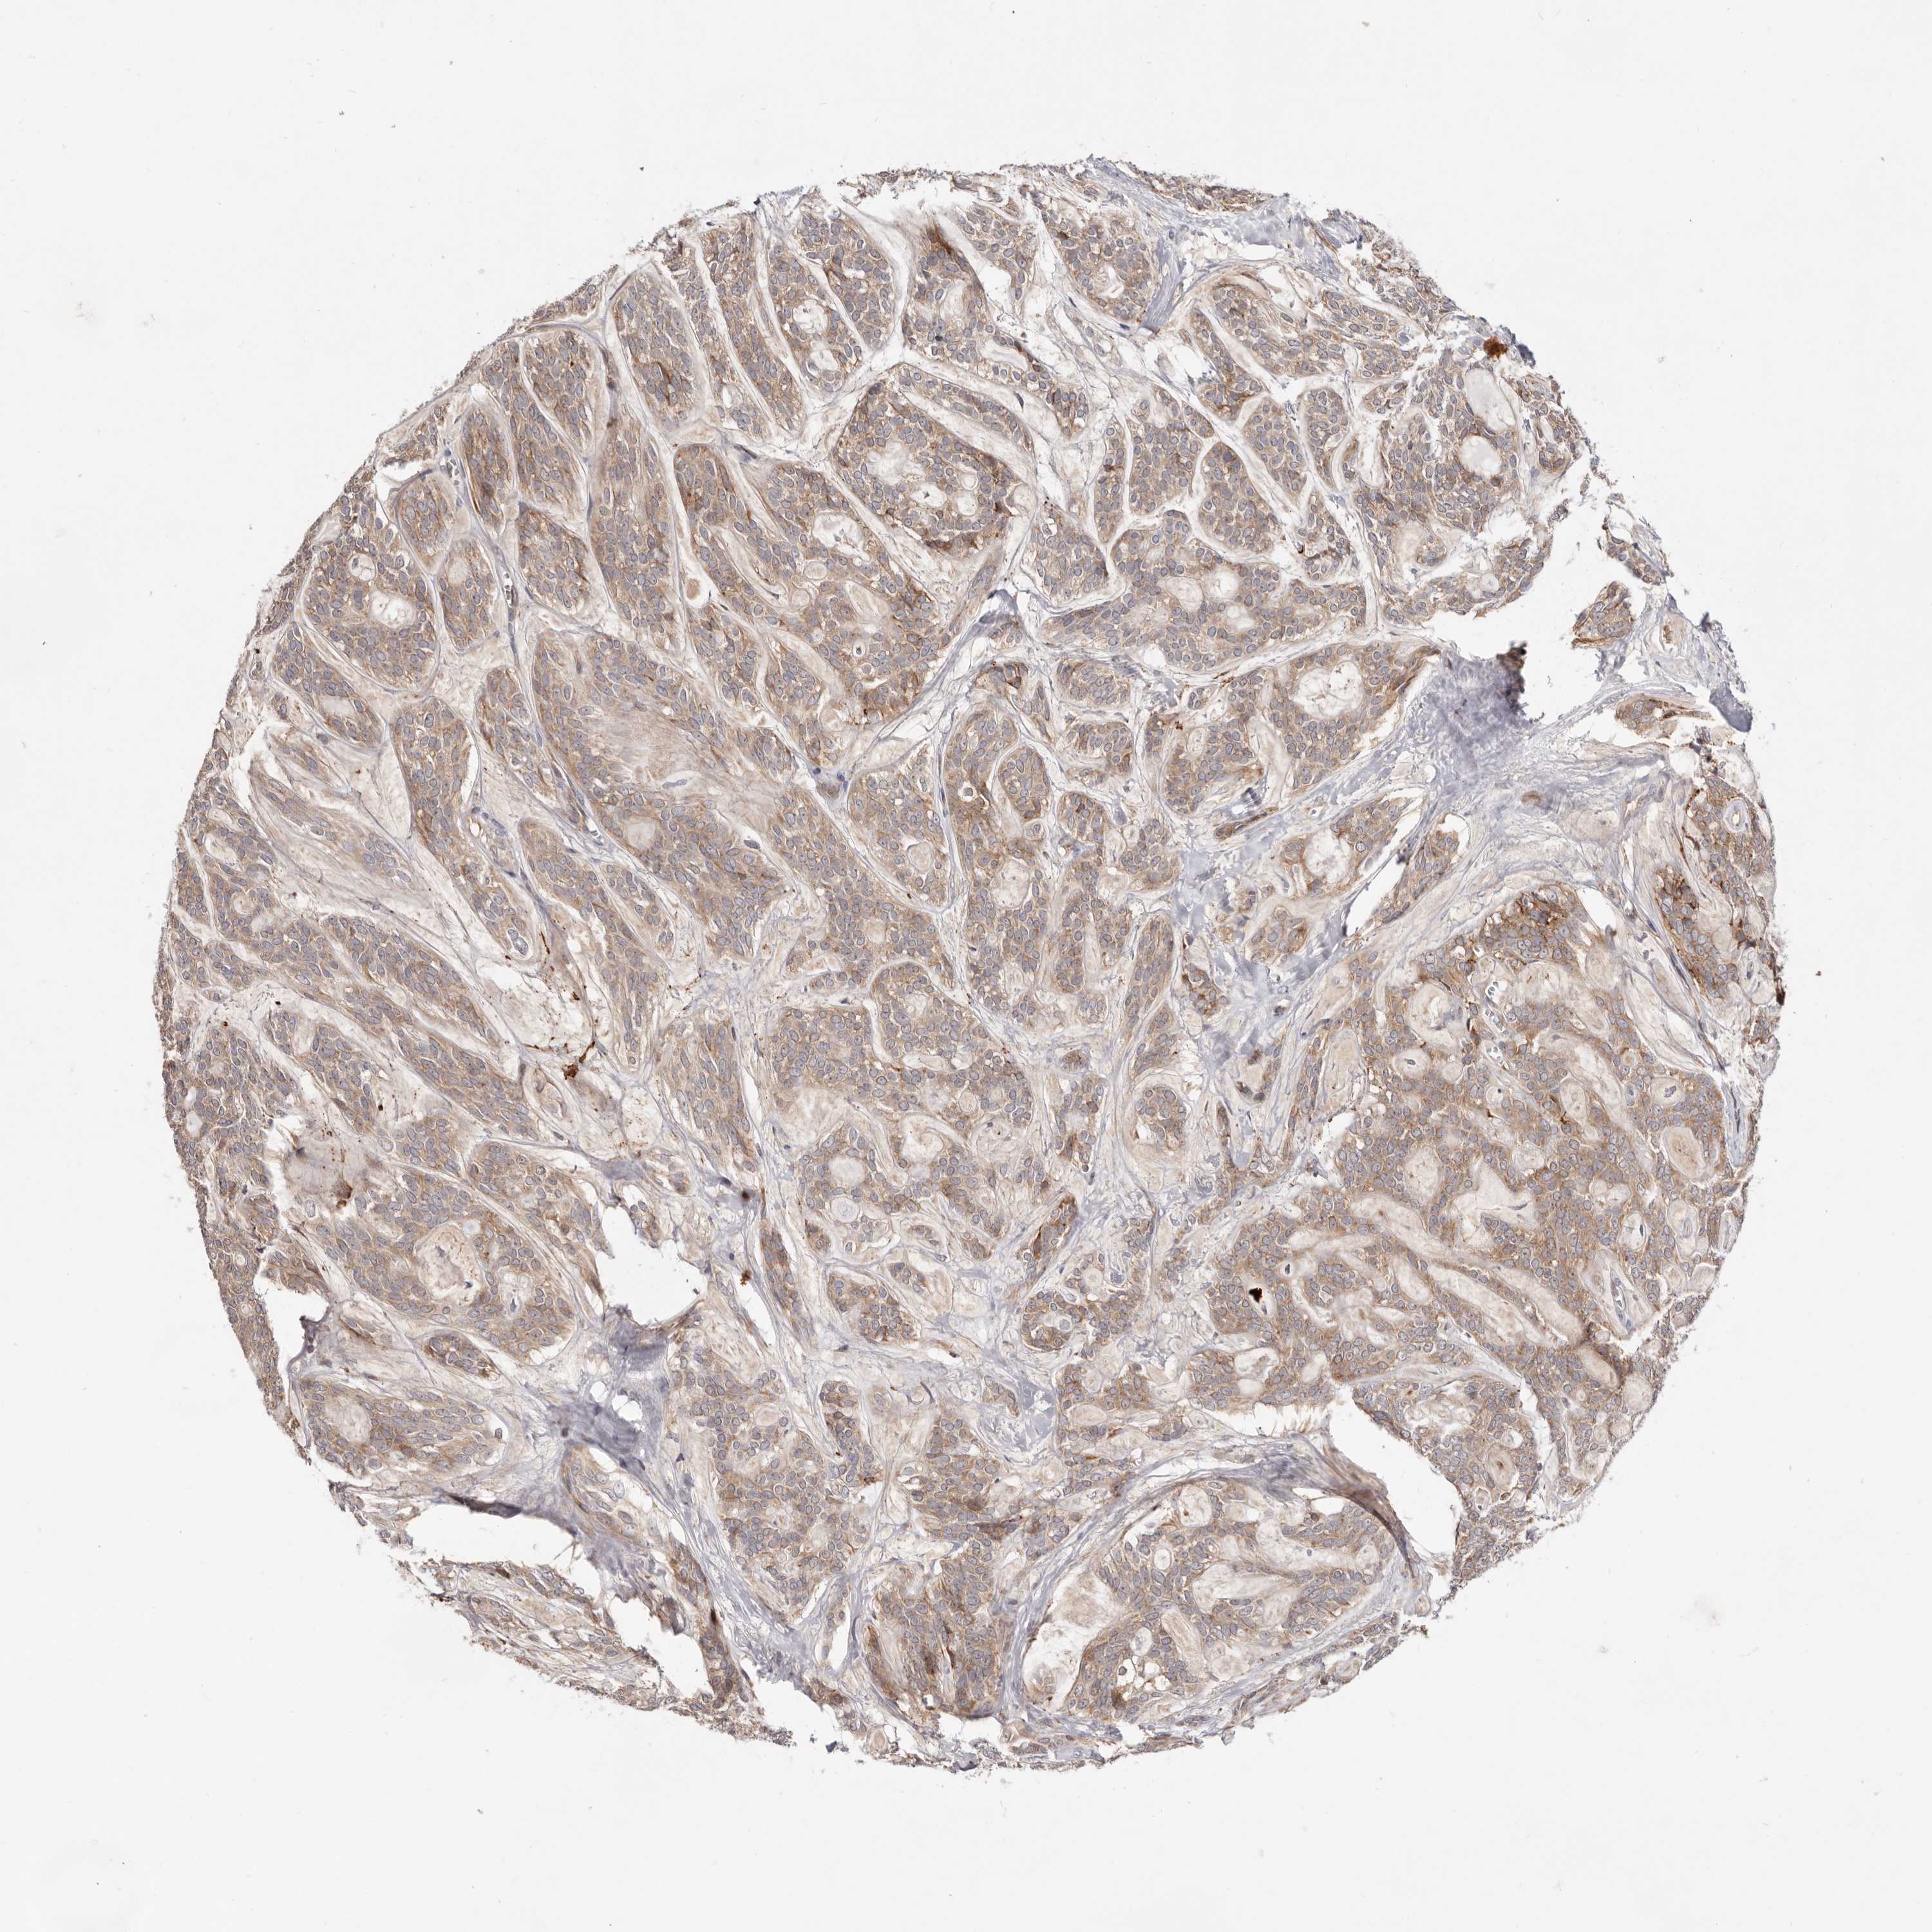

HEAD AND NECK CANCER - Protein expressioni

A mouse-over function shows sample information and annotation data. Click on an image to view it in a full screen mode. Samples can be filtered based on level of antibody staining by selecting one or several of the following categories: high, medium, low and not detected. The assay and annotation is described here.

Antibody stainingi

Antibody staining in the annotated cell types in the current human tissue is reported as not detected, low, medium, or high, based on conventional immunohistochemistry profiling in selected tissues. This score is based on the combination of the staining intensity and fraction of stained cells.

Each image is clickable and will lead to virtual microscopy that enables deeper exploration of all samples and also displays staining intensity scores, fraction scores and subcellular localization as well as patient and tissue information for each sample.

Antibody HPA026790

Staining

High

Medium

Low

Not detected

Intensity

Strong

Moderate

Weak

Negative

Quantity

>75%

75%-25%

<25%

None

Location

Nuclear

Cytoplasmic/membranous

Cytoplasmic/membranous,nuclear

Squamous cell carcinoma, NOS